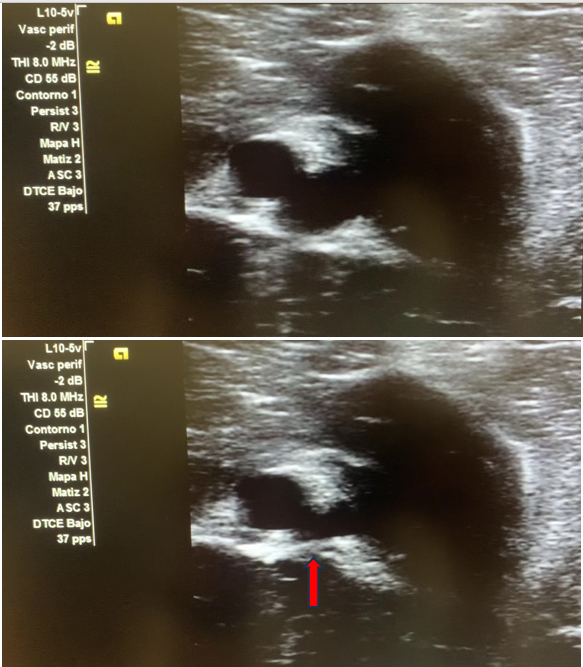

Imagen 2. Vasos no colapsables, con internior anecoico.

Imagen 3. Tono pulsátil de la fistula arteriovenosa.